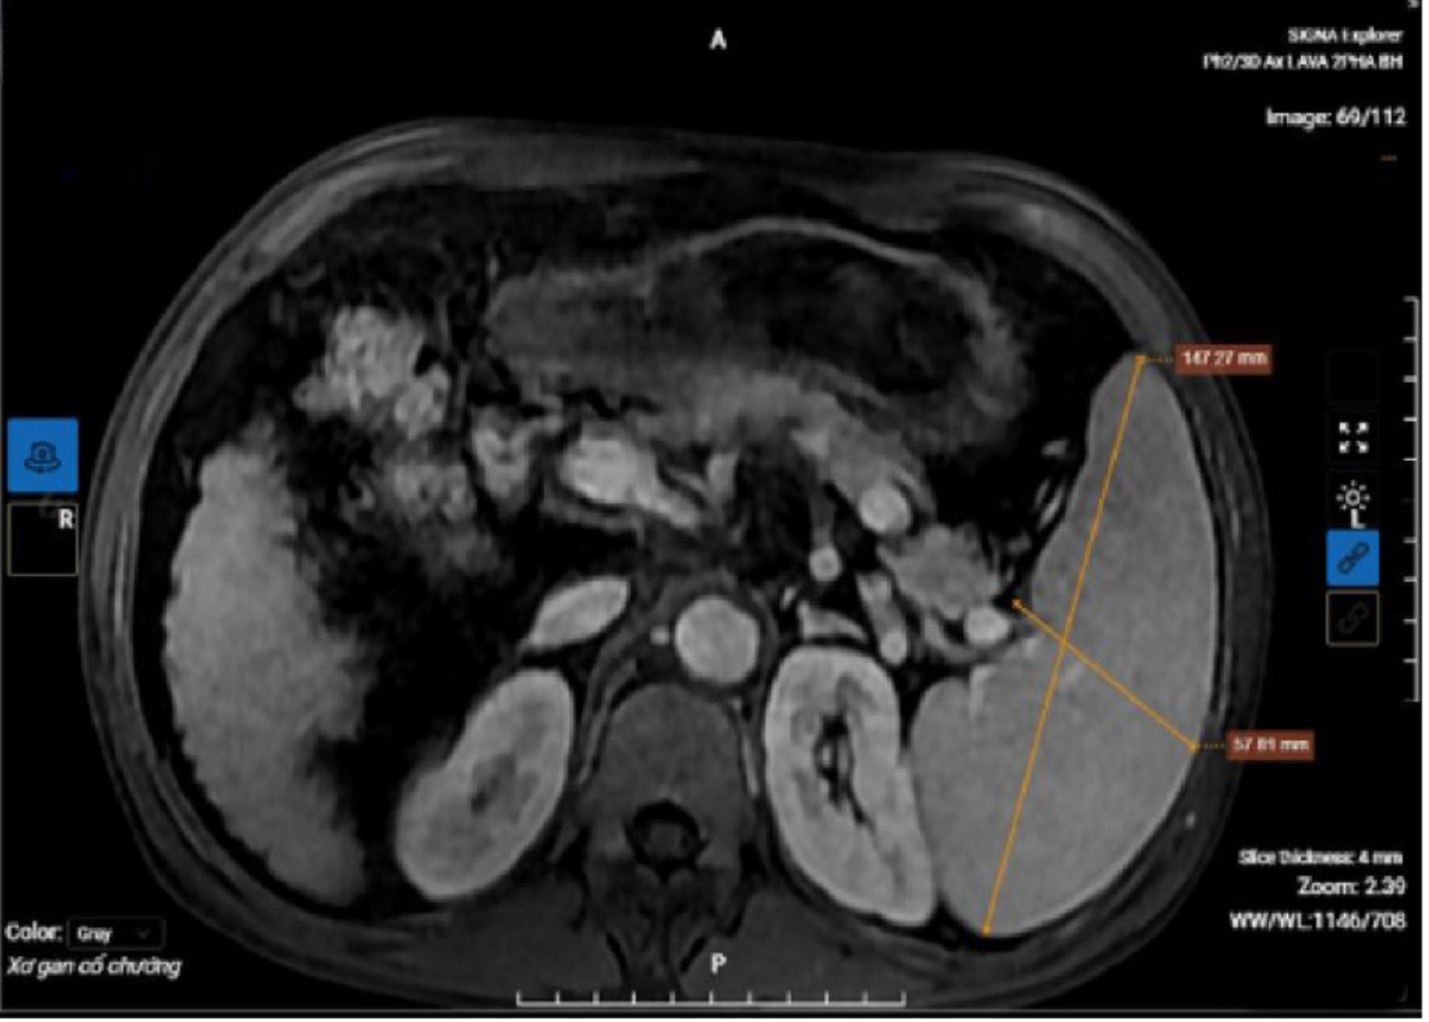

Mới đây, tại Phòng khám Đa khoa Medlatec Thanh Xuân (Hà Nội), ông N.V.A. (60 tuổi, Lạng Sơn) đến khám sức khỏe tổng quát trong tình trạng mệt mỏi, nước tiểu màu vàng đậm.

Kết quả chụp MRI của bệnh nhân cho thấy hình ảnh xơ gan lách to, dịch bao quanh gan.

Sau khi thăm khám lâm sàng và thực hiện các xét nghiệm, chẩn đoán hình ảnh cần thiết, kết quả cho thấy chỉ số men gan AST, ALT, Bilirubin trong máu của ông tăng ở mức báo động, cùng tình trạng xơ gan mất bù, kèm theo dịch ổ bụng.

Đồng thời, kết quả xét nghiệm của bệnh nhân còn cho thấy dương tính với viêm gan B. Cuối cùng, bác sĩ đưa ra chẩn đoán xác định bệnh nhân mắc xơ gan mất bù kèm viêm gan B mạn tính.

Kết luận về trường hợp này, TS.BS Ngô Chí Cương - Phó Giám đốc chuyên môn Bệnh viện Đa khoa Medlatec, Trưởng Chuyên khoa Truyền nhiễm và Y học Nhiệt đới, cho biết, bệnh nhân sẵn có tiền sử xơ gan nhưng không điều trị dẫn đến tình trạng xơ gan mất bù trầm trọng.